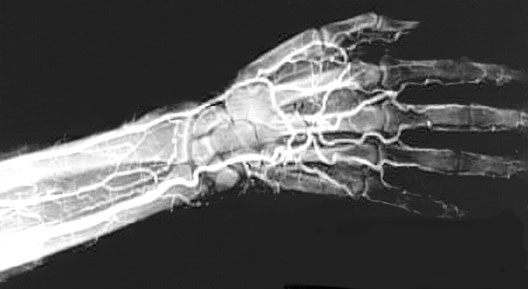

Arm and Hand Angiogram

1. Radial Artery

2. Ulnar Artery

3. Deep Palmar Arch

4. Common Palmar Digital Artery

5. Proper Palmar Digital Artery